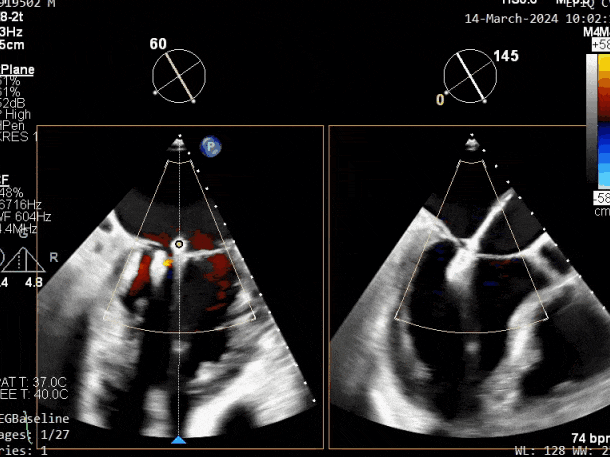

PISA法测r=12mm,EROA=0.72cm2,RVOL=100ml,RF 26%。LVEDD 57mm,左房71*59*77mm,右房55*69mm,LVEF 70%。

二尖瓣反流(重度,4+级,Carpentier I型)

瓣膜夹释放前评估,二尖瓣反流减轻

瓣膜夹释放前评估,二尖瓣平均跨瓣压差及瓣口面积

释放瓣膜夹后评估,二尖瓣呈双孔,外侧仍有残余反流

第三个瓣膜夹释放后评估,释放后评估,二尖瓣呈双孔,组织桥张力合适,瓣膜夹轴向与二尖瓣闭合线垂直,无残余反流

肺静脉血流频谱恢复为收缩期正向